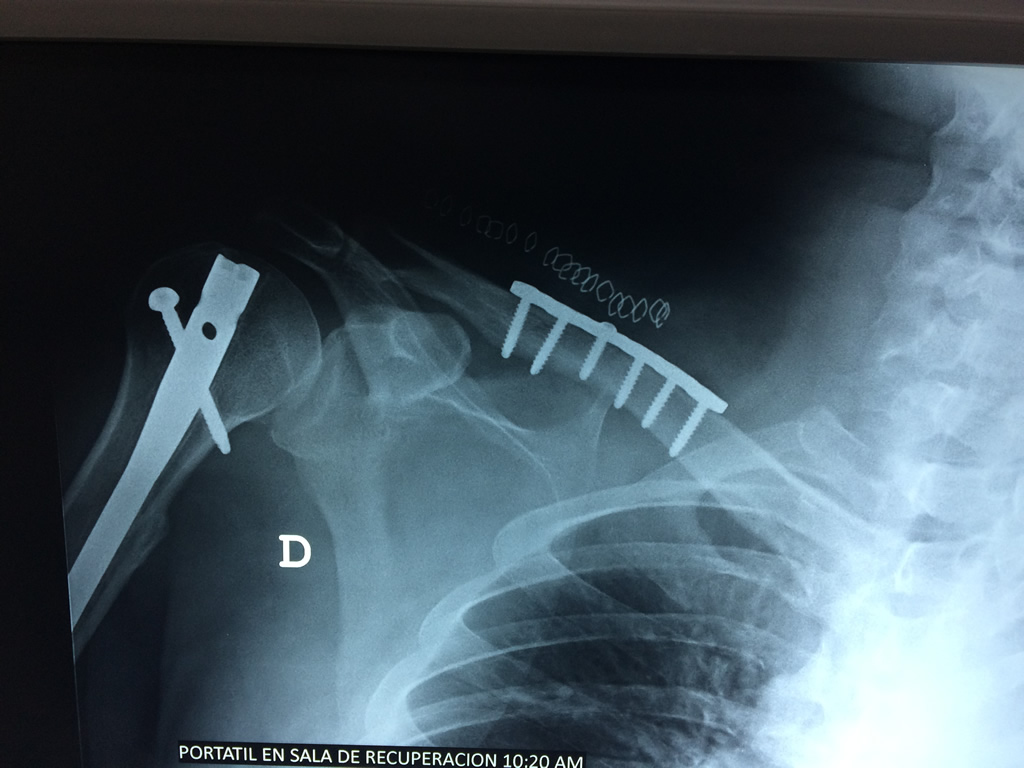

Cirugías de Calcaneo - Clavícula

La clavícula es un hueso largo, con forma de "S" itálica, situado en la parte anterosuperior del tórax. Junto con la escápula forman la cintura escapular. Se puede palpar por toda su longitud y se extiende del esternón al acromion de la escápula, siguiendo una dirección oblicua lateral y posterior.